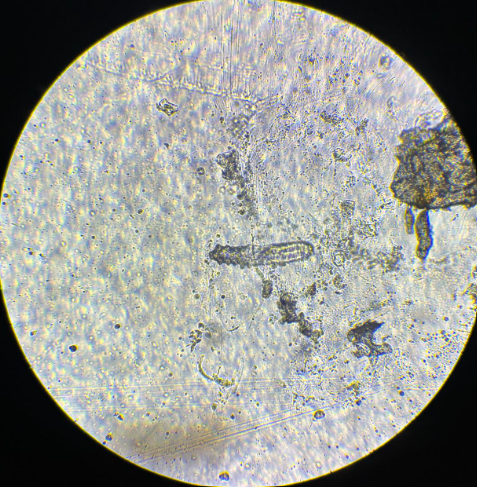

demodex sp imago